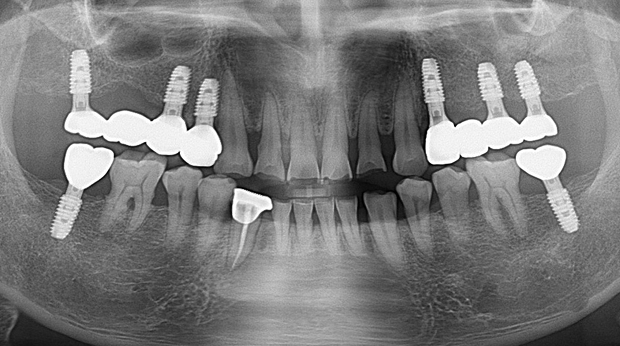

의식하진정법(수면마취)/임플란트

수술 담당 구강악안면외과 전문의

고난도 수술 진료

임플란트와 사랑니 발치는 외과적 시술로 잇몸을 절개하는 외과적 시술은

치과의사 경력 14년차 구강외과 전문의가 빠르고 안전하게, 아프지 않게 수술해 드립니다.